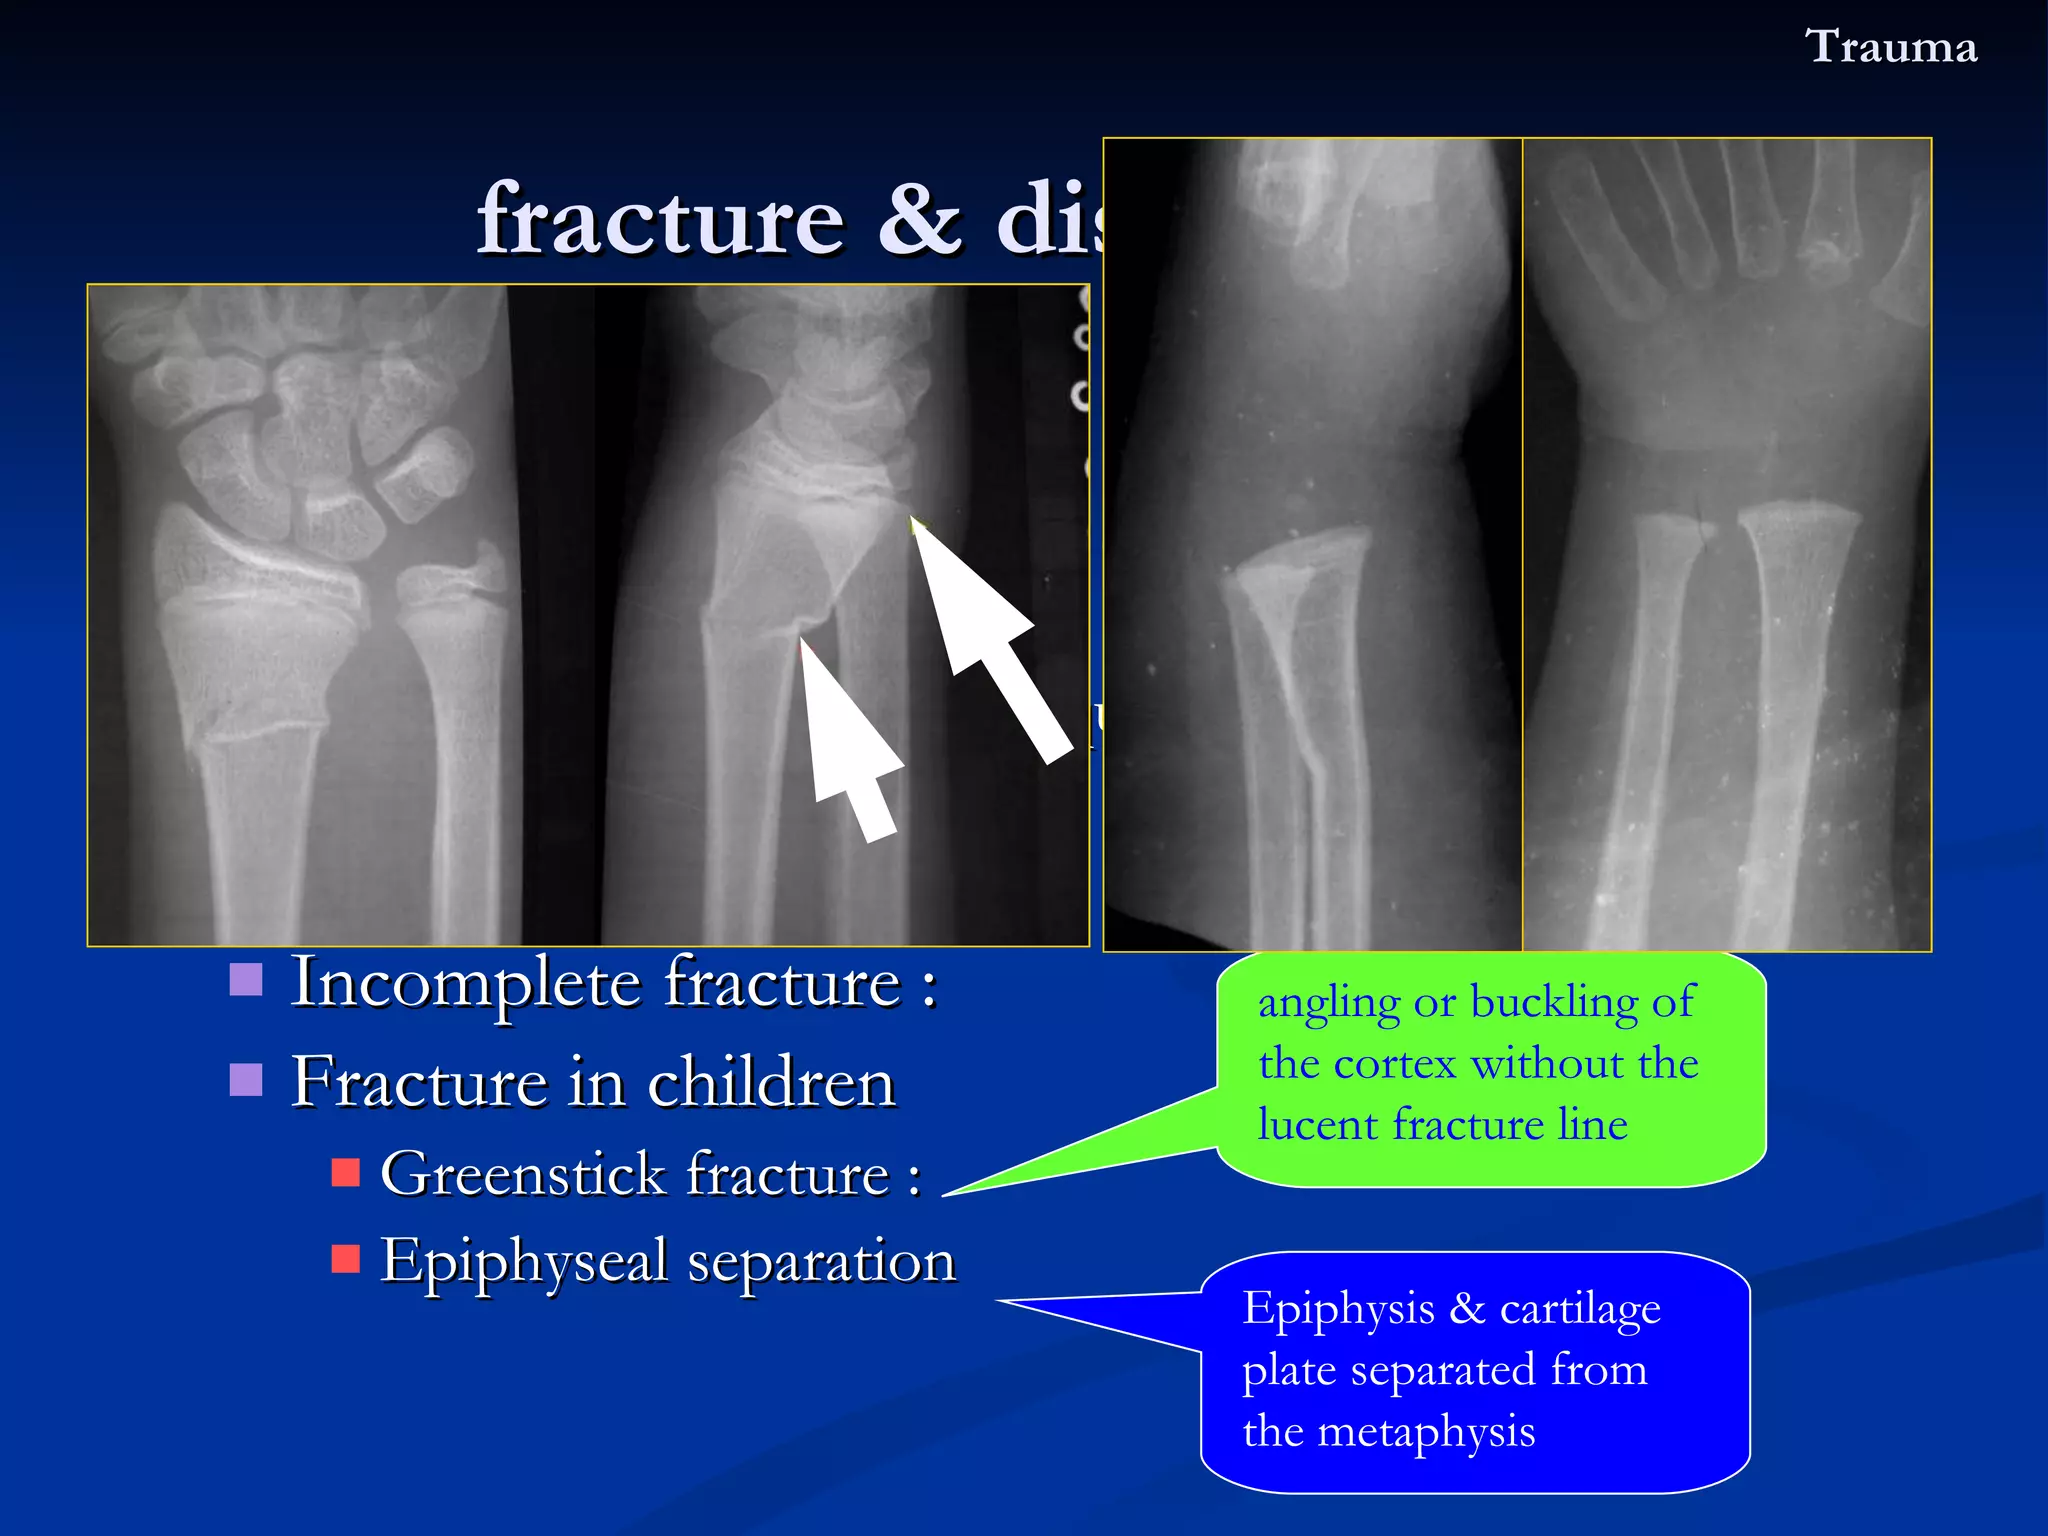

Colles ’  fracture A transverse fracture  through the distal radius With dorsal displacement & angulation of the distal radial fragment Malalignment as  “ silver fork ”   deformity The ulnar styloid is often detached Fracture & dislocation  Trauma